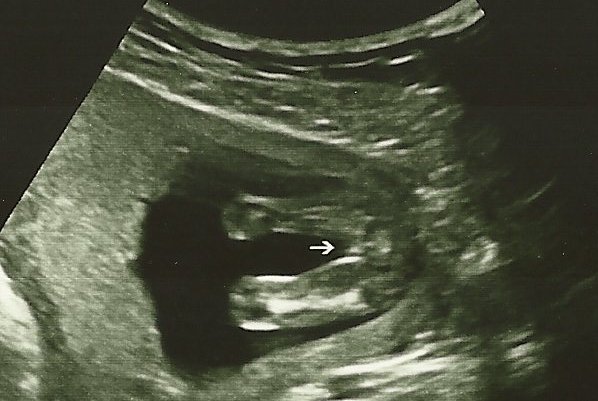

what does this baby look like to you? she told me she was 100% sure on what she told me and also that she has never been wrong in 13 years so please take a guess at my baby's gender to ease my mind!!!Attachment 13058

thanks everyone!!! i was 15+4 but the baby was measuring 16+1 and she def said it was a girl lol!!! she wrote on the picture "im a girl for sure"